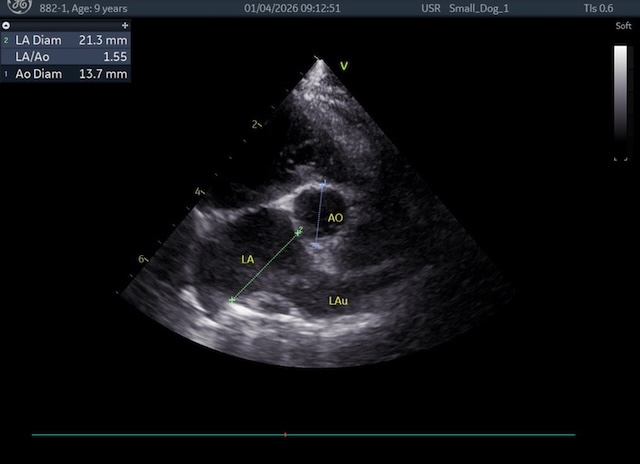

術後は、逆流も消失し、左心房、左心室がかなり小さくなってくれました。